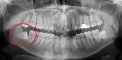

Arkadaşlar gömülü diş tedavisi olacğım da bu konuda bilgiis olon var mı? hastane tıp fkültesine zevk etti. 20 lik gömülü dişi doktor tedavi edemiyeceğini sevk edeceğini soyledi. ben de ilk defa gömülü diş tedavisi olacğım. Böyle birşeyle karşılaşan arkadaşlar var mı? tedavis nasıl yapılmaktadır?

4 diş aldırdım bu şekilde